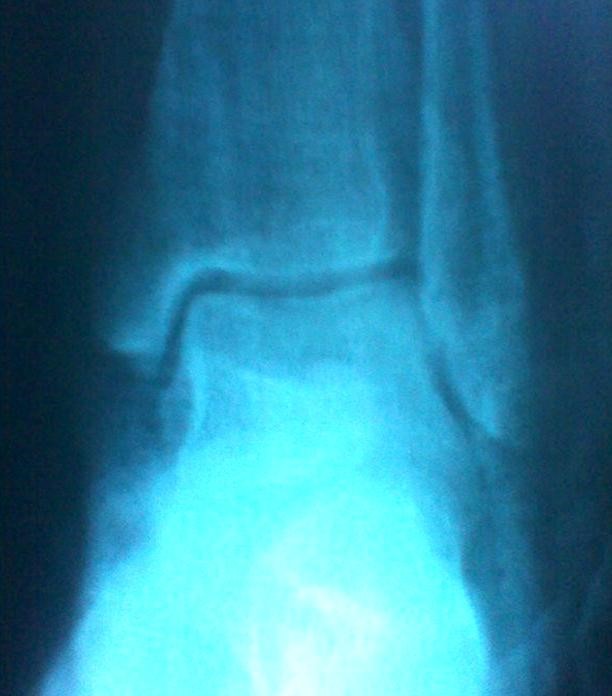

Volver a los detalles del artículo Luxación subastragalina medial